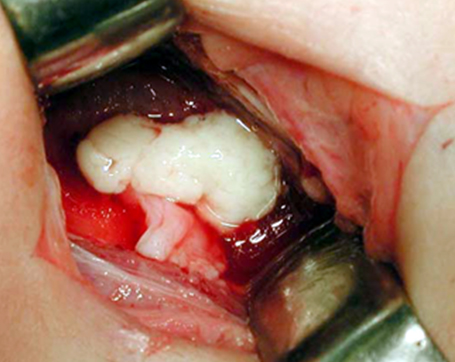

関節切開・排膿

手術にて股関節の切開を行うと、膿の排出がみられる。